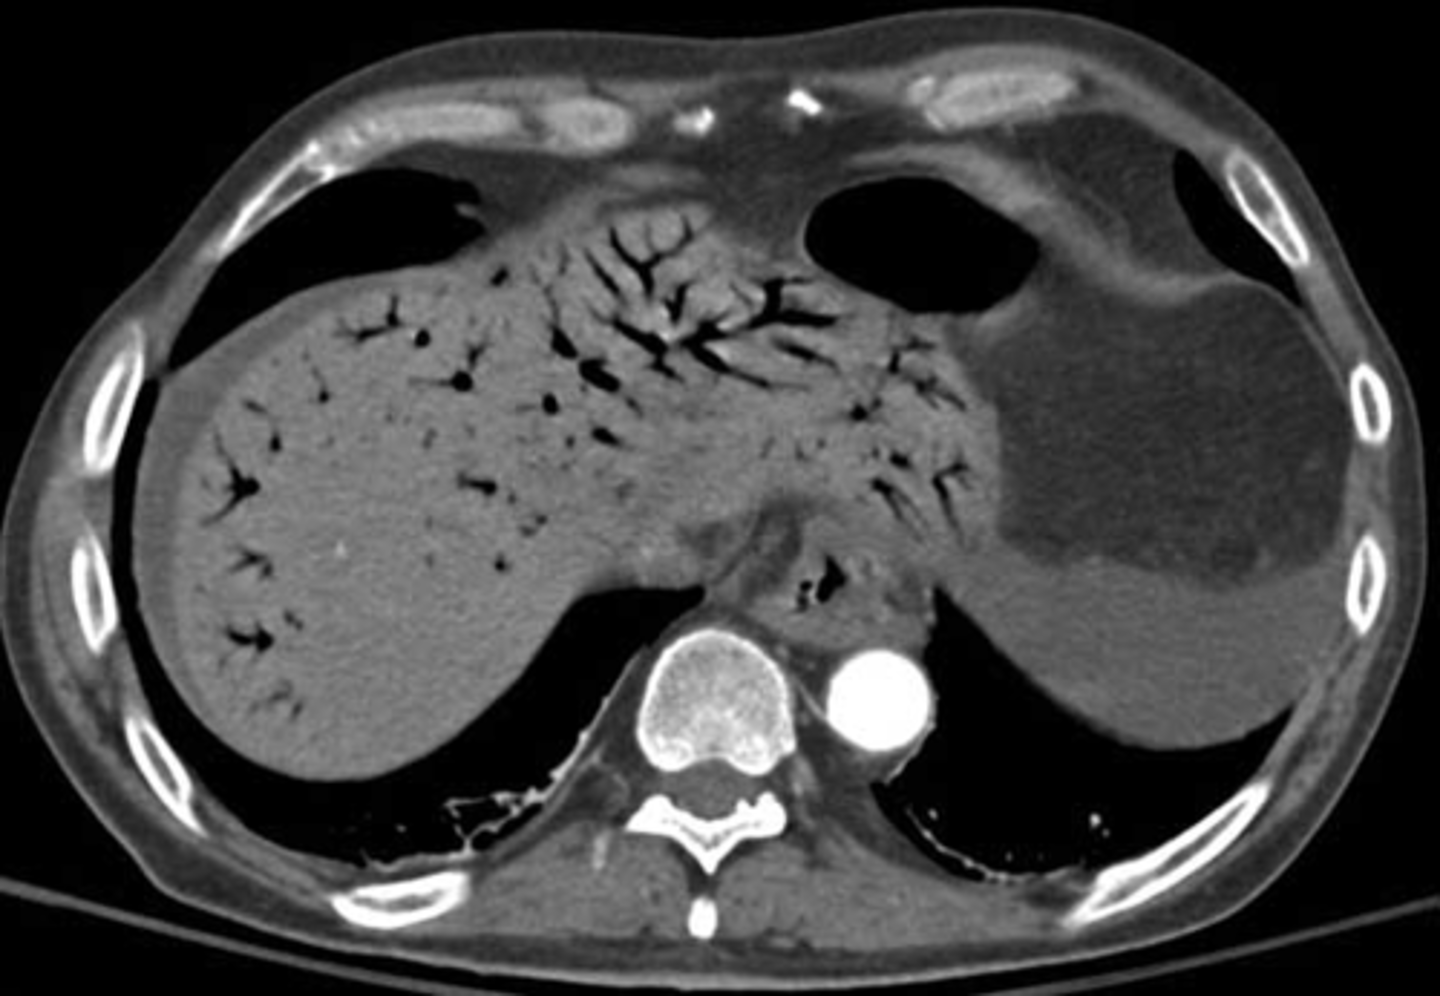

Portal air in liver secondary to pneumatosis